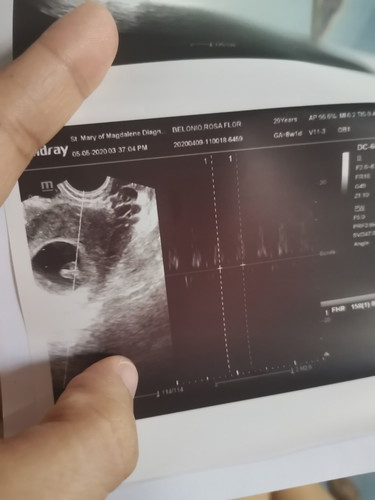

Share ko lang story ko. Nagpositive PT ako pero may brown spotting ako. Rushed to OB, nagpa TVS (4weeks na pala ako) and diagnosed sakin I'm having threatened abortion, miscarriage or ectopic pregnancy. Wala man lang pampalubag na may tyansa magtuloy pregnancy ko. Umuwi akong umiiyak noon. After 2 weeks (6weeks na ko. Nagsspotting parin ako.), repeat ultrasound ako (kasi ayokong pumayag na tama ang OB sa assumptions nya). Result ng TVS ko, GS lang. Walang fetal pole. Sabi pa ng OB Sonographer and I quote, "mukhang hindi tutuloy ito". I was heartbroken again. Pero sabi ko babalik ulit ako. I was the one pa nga humingi ng pampakapit sa OB ko kasi wala man lang syang advise na ganon na mag take ako. After 2 weeks (8 weeks na ko from LMP. Nagsspotting parin). TVS result. Ito na nga. Nagpakita na ang baby ko. May bonus pang healthy heartbeat! I was so happppppy! Nag develop siya. Kumapit sya. Hindi ako iniwan ng baby ko. I am in tears after ng TVS ko. Hindi ko inexpect. Thank you Lord! You are so good! We kept on praying together with our family abt my pregnancy. Dumating na ko sa point ng prayer ko na, "Lord, kung hindi po para sa amin, kunin nyo na po siya". Pero hindi ako pinabayaan ni Lord. Prayer works! Salamat sa mga magbabasa. Wag tayo mawawalan ng pag asa. Fighting!